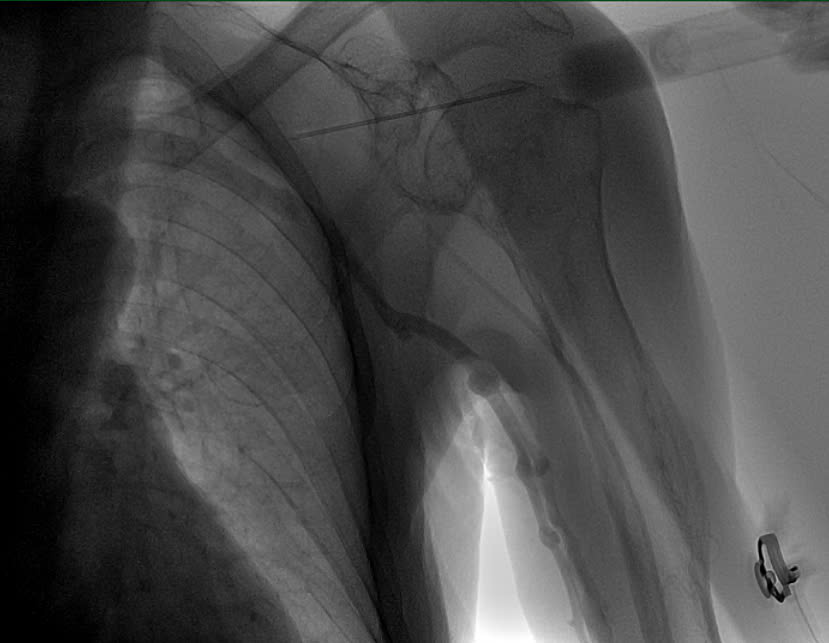

Phương pháp chọc tĩnh mạch dưới đòn có dẫn đường bằng chụp tĩnh mạch dưới màn hình tăng sáng

Để đảm bảo an toàn tối đa, ekip đã lựa chọn phương pháp chọc tĩnh mạch dưới đòn có dẫn đường bằng chụp tĩnh mạch dưới màn tăng sáng (fluoroscopy). Đây là kỹ thuật hiện đại, cho phép định vị chính xác vị trí tĩnh mạch trong những cơ địa khó, giảm thiểu nguy cơ tổn thương mạch và các biến chứng khác. Tư thế và kỹ thuật chọc kim cũng được điều chỉnh linh hoạt để phù hợp với tình trạng gù vẹo của bệnh nhân.